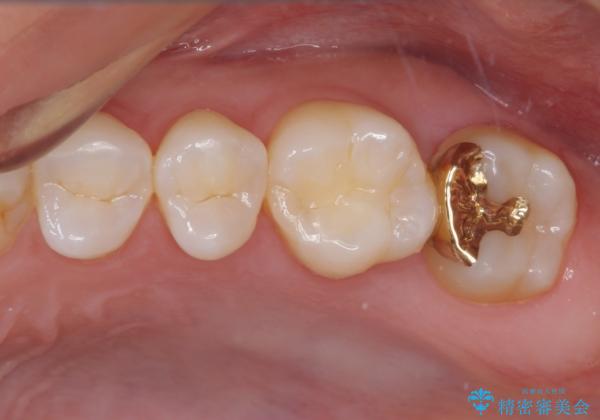

ゴールドインレーは銀歯のインレーやセラミックインレーと比べ、「技工操作の精度が高く、適合が著しく良い」というメリットがあります。特に上の奥歯は歯科医師の操作が行いにくいため、「適合の良さ」は再治療のリスクを防ぐ上でとても重要な要素となります。

上の奥歯は金属色が見えることもないため、審美的な問題は全くありません。

咬み心地はとても良好で、全く違和感がなく、患者様には大変満足していただきました。